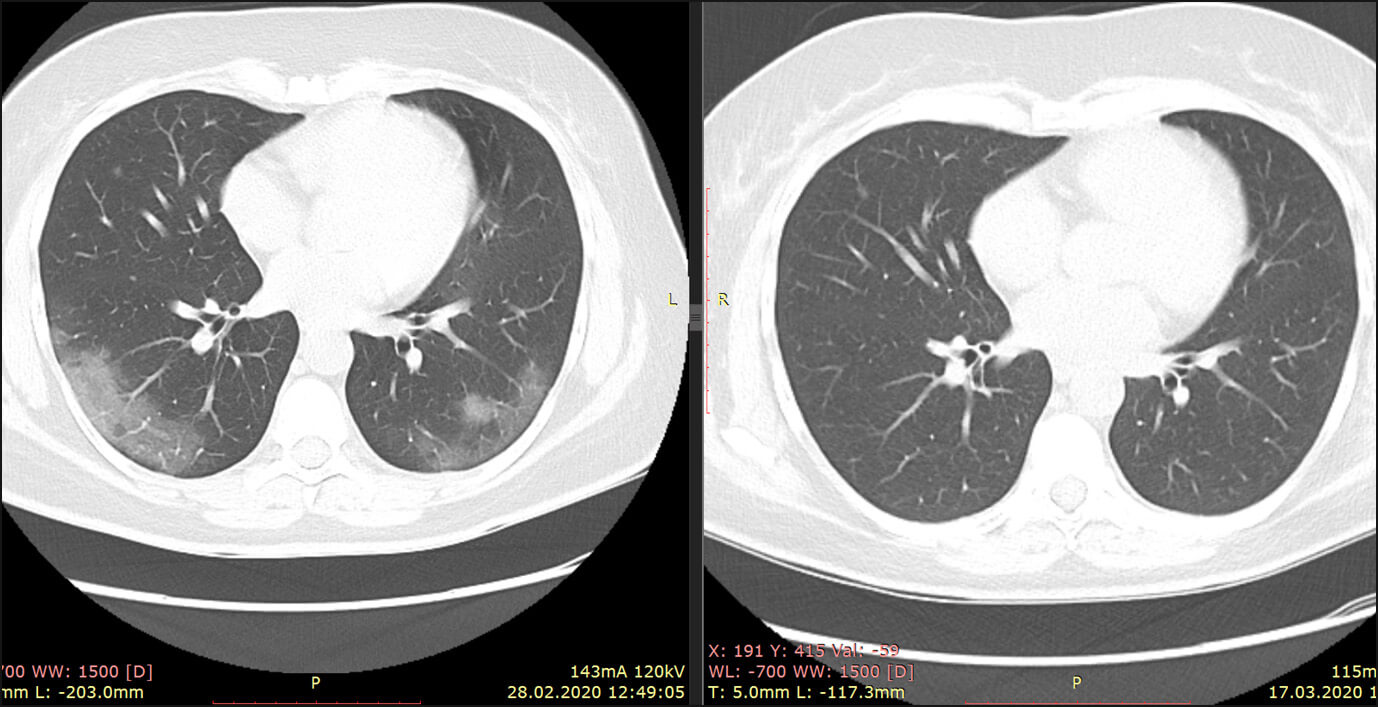

Если объяснять совсем просто, все потому, что при ковиде в легких наблюдается так называемая «ковидная тишина» – не слышно ни вдоха ни выдоха. Это происходит, так как при COVID-19 альвеолы в легких набухают и отекают. А при бактериальной пневмонии альвеолы наполняются мокротой и врач при вдохе/выдохе слышит хрипы. Подобные пневмонии лечатся антибиотиками. Ковидная – нет.

Ковидная пневмония сильно отличается от бактериальной